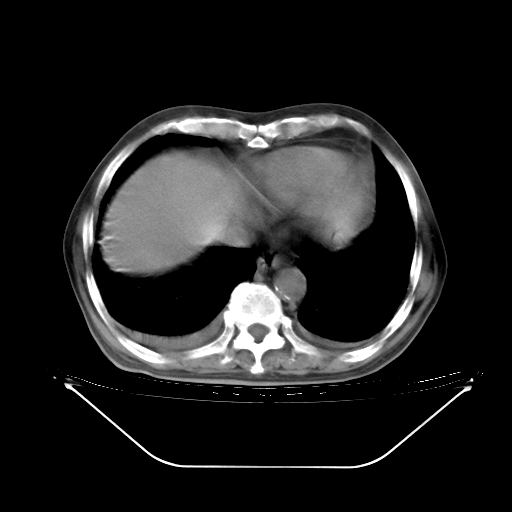

今天复查肺部CT,发现双肺广泛磨玻璃样改变。所以我把3月19日和5月9日相隔50天的肺部CT上传。请大家会诊。

2009年3月19日肺部CT片。

2009年3月19日肺部CT